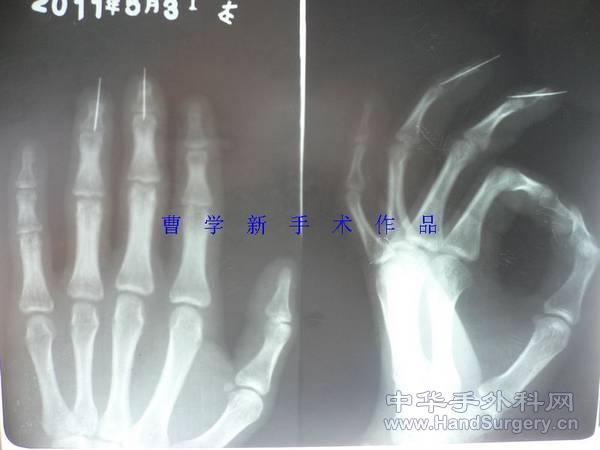

[断指再植] 双手五指完全离断再植(两年随访照来啦)

RE: 双手五指完全离断再植(更新术后三个月随访)

本帖最后由 xinge78713000 于 2011-8-20 12:29 编辑